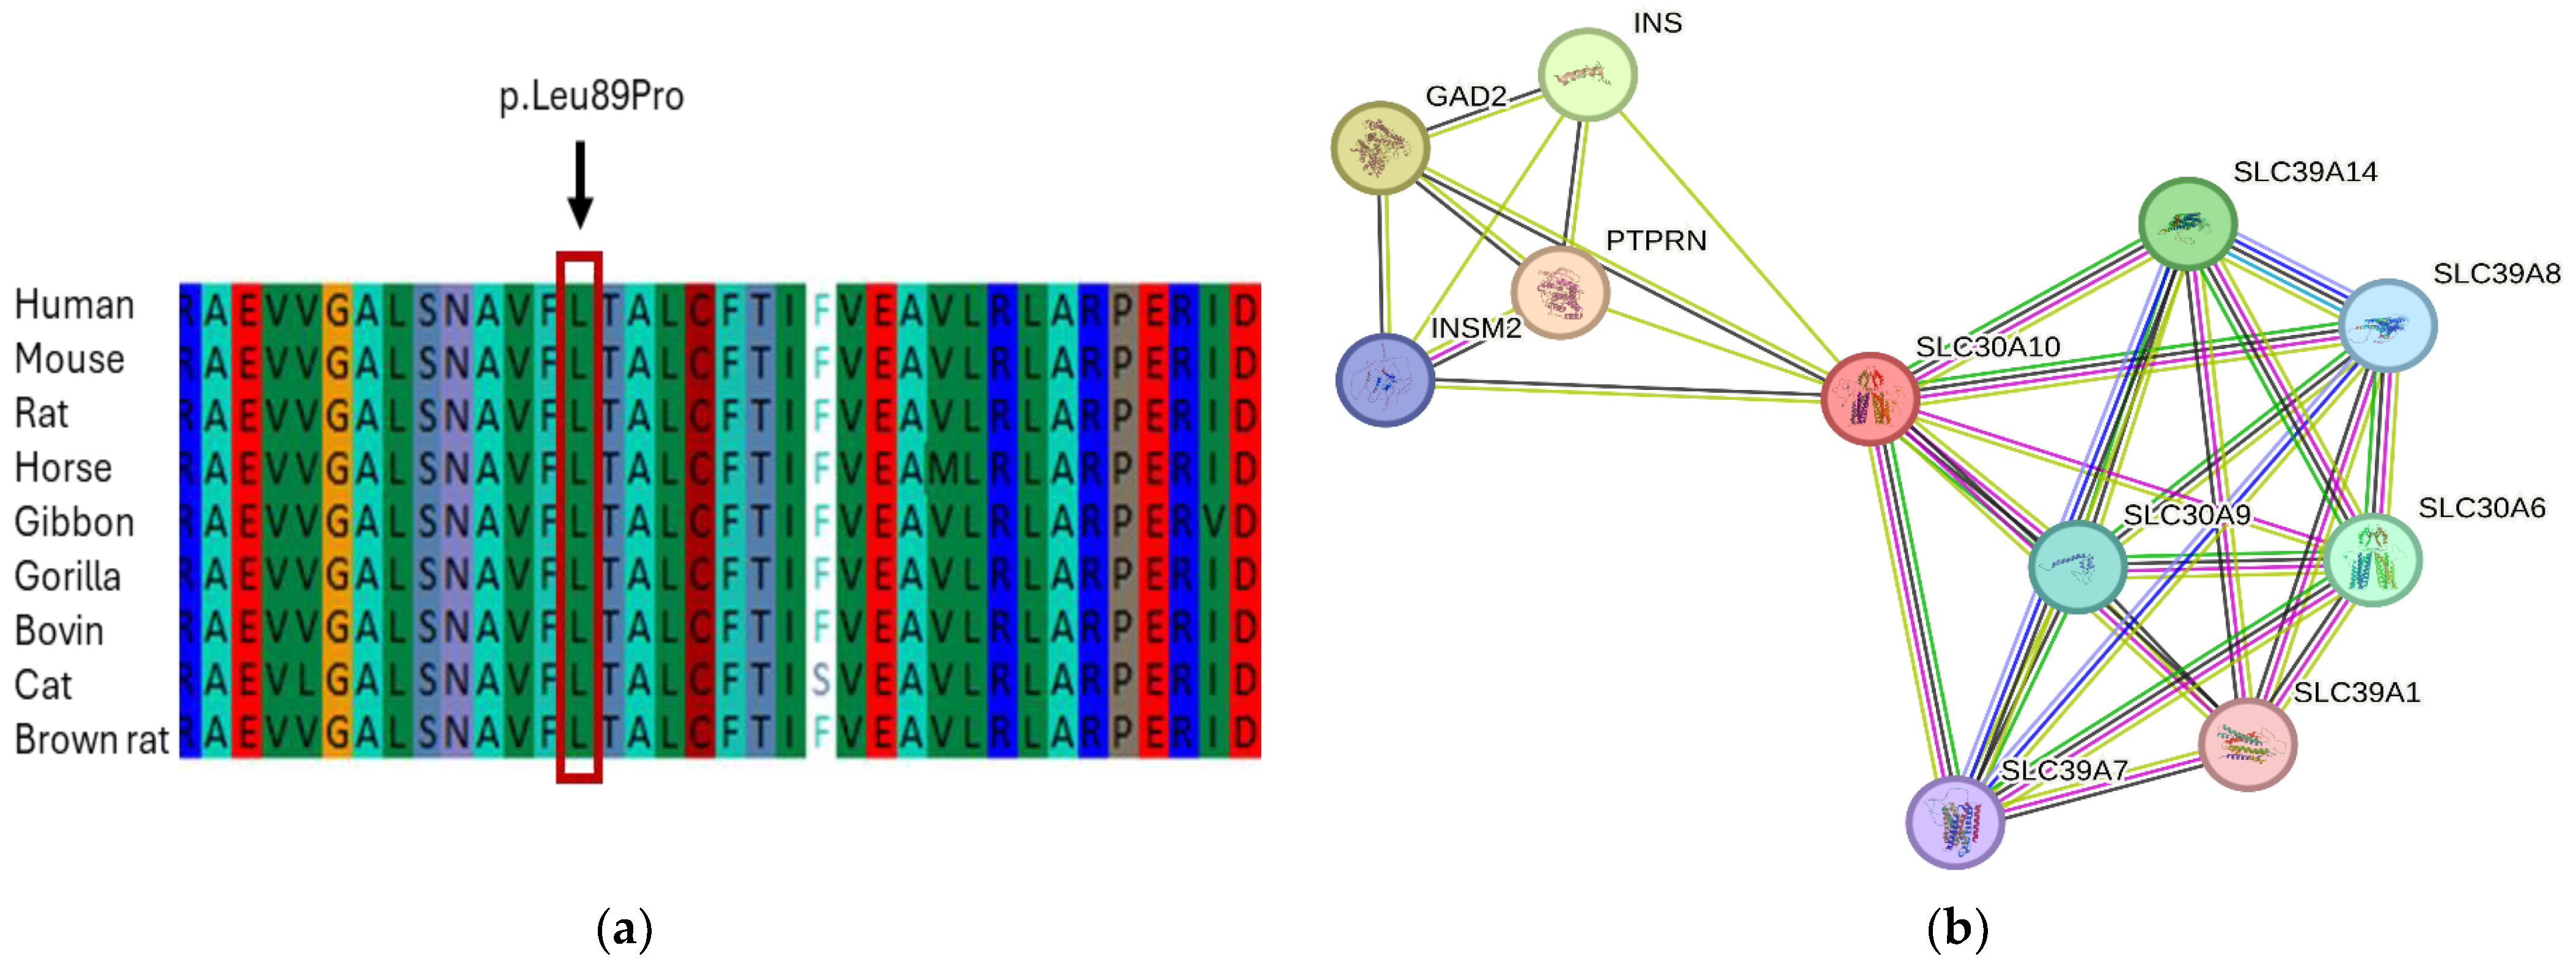

3.4. In Silico Analysis and Protein Network Interaction